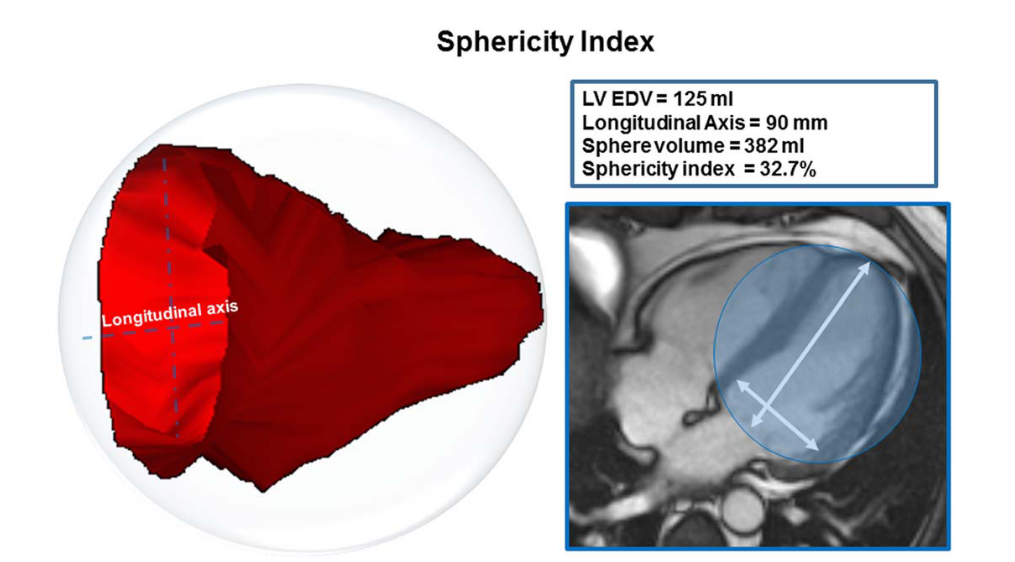

The sphericity index is calculated at end-systole and end-diastole as the volume of the left ventricle divided by the volume of a sphere whose diameter is equal to the longitudinal diameter (major axis of the ventricle). As this ratio increases, the shape of the left ventricle approaches that of a sphere (Kono et al., 1991).

(Aquaro et al., 2017)

(Aquaro et al., 2017)

For patients with dilated cardiomyopathy (DCM), the more spherical LV chamber is shown by a few studies to be associated with higher end-systolic wall stress, an abnormal distribution of fiber shortening and a poor long-term survival. In patients with heart failure due to either coronary artery disease or dilated cardiomyopathy and LVEF <= 30%, a more spherical LV chamber is associated with the presence of functional MR (Kono et al., 1991).